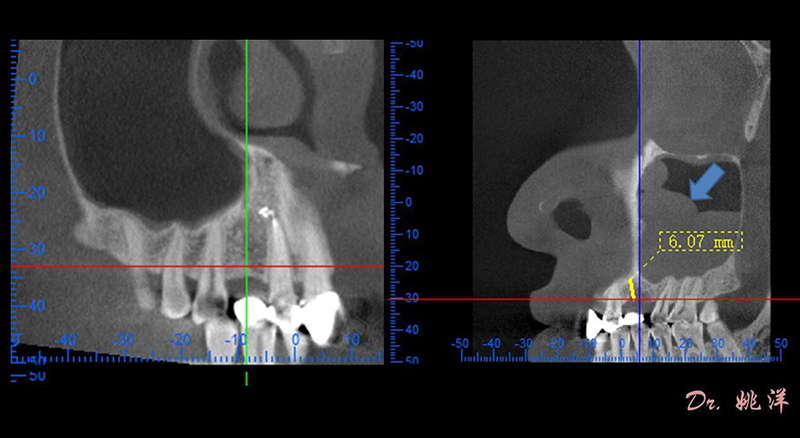

觀察患者CT,可看出患者有上頜竇粘膜囊腫,粘膜囊腫為竇內(nèi)腺體阻塞所致,視情況可有手術(shù)摘除和不予處理兩種方法,此次患者拒絕手術(shù)摘除,故需規(guī)避上頜竇位置。

冠狀面視圖

矢狀面視圖

根據(jù)患者CT顯示,使用種植導(dǎo)航軟件設(shè)術(shù)前手術(shù)方案??紤]到患者拒絕手術(shù)摘除上頜竇囊腫等因素,此次手術(shù)選用了Straumann骨水平4.10*8.0mm的植體,植體末端位點(diǎn)設(shè)計(jì)距上頜竇底壁2mm處的同時(shí)兼顧種植方向和修復(fù)間隙,來(lái)達(dá)到理想的效果。